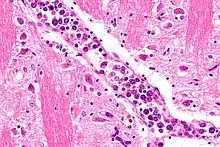

Micrograph showing an intravascular large B-cell lymphoma in a blood vessel of the brain. H&E stain. | |

The diagnosis of IVBCL is heavily dependent upon obtaining biopsy specimens from involved tissues, particularly the skin but in cases without skin lesions, other apparently involved tissues. Microscopic examination of these tissues typically shows medium-sized to large-sized lymphocytes located within small- to medium-sized blood vessels of the skin, lung, and other tissues or the sinusoids of the liver, bone marrow, and spleen. On occasion, these malignant cells have the appearance of Reed-Sternberg cells. The lesions should show no or very little extension outside of blood vessels. As determined by immunohistochemistry analyses, the intravascular malignant lymphocytes express typical B-cell proteins, particularly CD20, which is found in almost all cases, CD79a and Pax5, which are found in most cases,[5] and MUM1 and Bcl-2, which are found in 95% and 91% of cases, respectively.[2] These B-cells are usually (80% of cases) non-germinal center B-cells (see Pathophysiology section) and may express one or more of the gene, chromosome, and gene expression abnormalities described in the above Pathophysiology section. Since the classical variant can present with a wide range of clinical signs, symptoms, and organ involvements, its presence may not be apparent, particularly in cases that do not exhibit clinically apparent skin lesions. Accordingly, random skin biopsies have been used to obtain evidence of IVL in cases that have signs and/or symptoms of the disease that are restricted to non-cutaneous sites,[2] even in cases that present with no other finding except unexplained fever.[17] The diagnosis of IVBCL, classical variant is solidified by finding these pathological features in more than one site.[2]